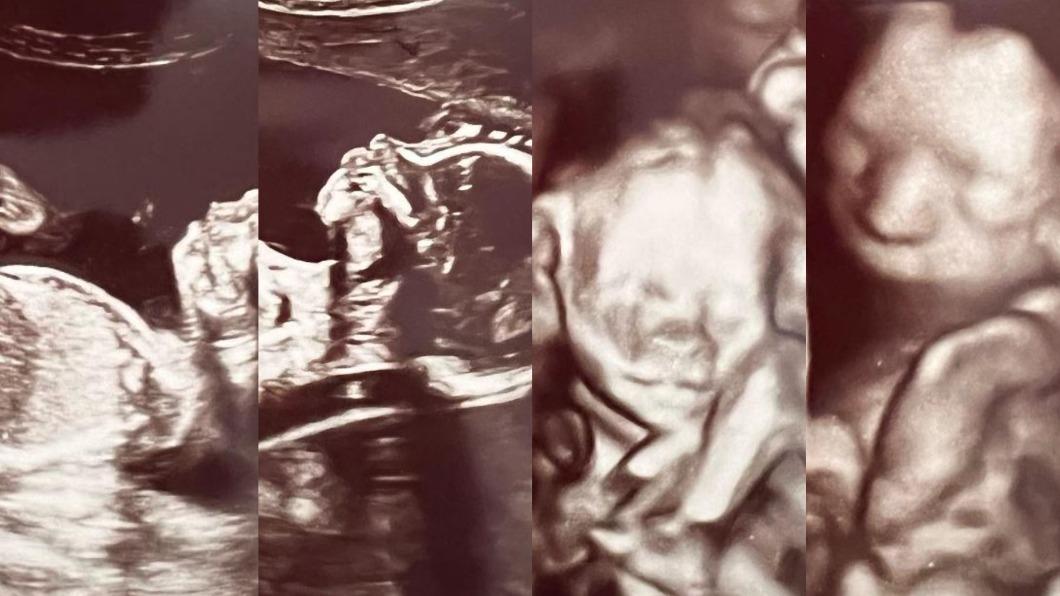

醫生接受採訪時表示他也從來沒有見過這種案例,「我當時還走出房間上網搜尋了一下才確定」,艾希莉透露她的母親有一對雙胞胎兄弟,祖父自己是雙胞胎,姑姑則是生了一對雙胞胎,而她男朋友的媽媽也是雙胞胎,因此兩人身上或許都有著生雙胞胎的基因吧!

(圖片來源:IG@ashleyjness)